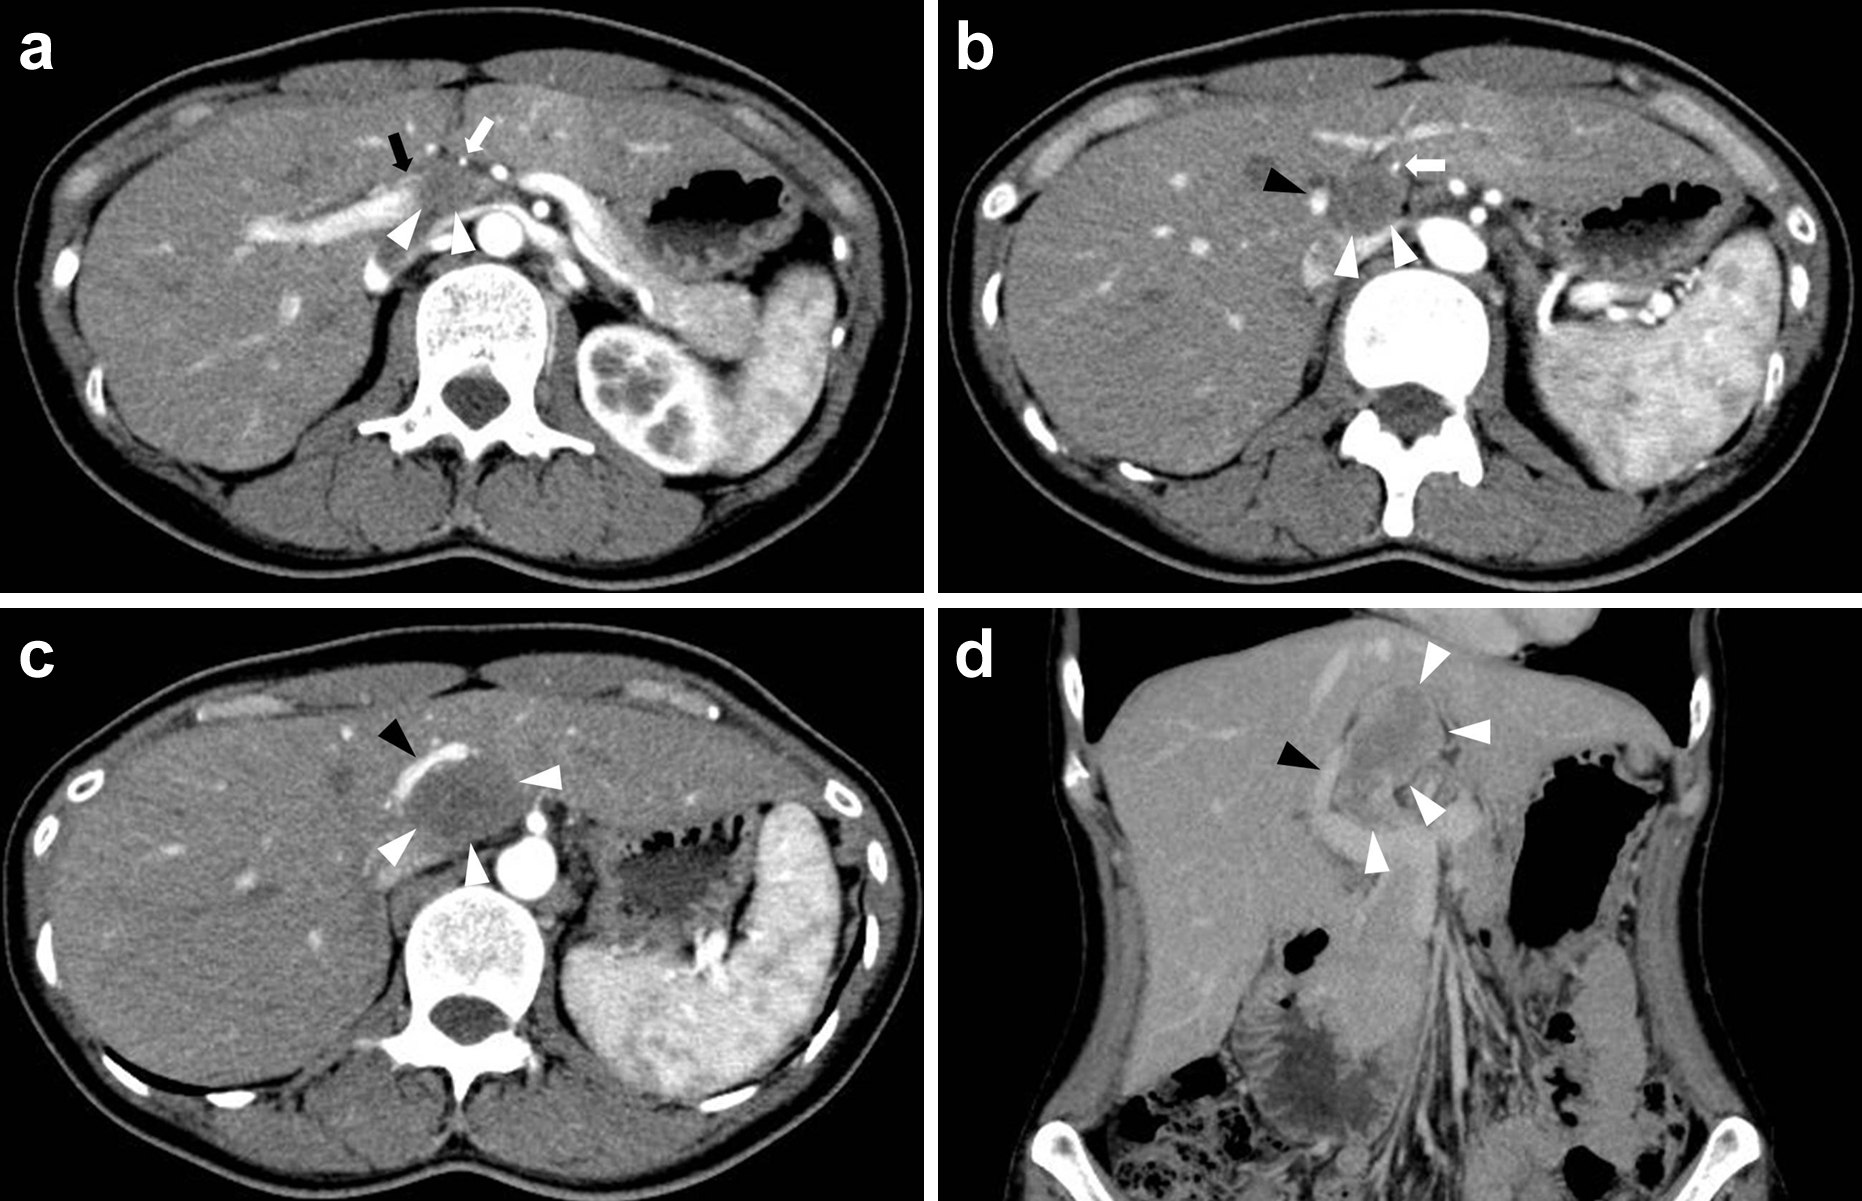

腹部造影CT所見(初診時より2年半後):肝尾状葉腹側に長径56 mmの比較的境界明瞭な腫瘤を認めた.辺縁より漸増性に淡く造影され,中心部は造影効果に乏しかった.腫瘤は左右肝動脈と門脈左枝を圧排していたが血流は保たれていた(Fig. 4).

(a–d) Abdominal contrast CT revealed a low density tumor on the ventral side of the hepatic caudal lobe, contacting the left and right hepatic artery and left branch of the portal vein directly (black arrow: right hepatic artery, white arrows: left hepatic artery, black arrowheads: left branch of portal vein, white arrowheads: tumor).